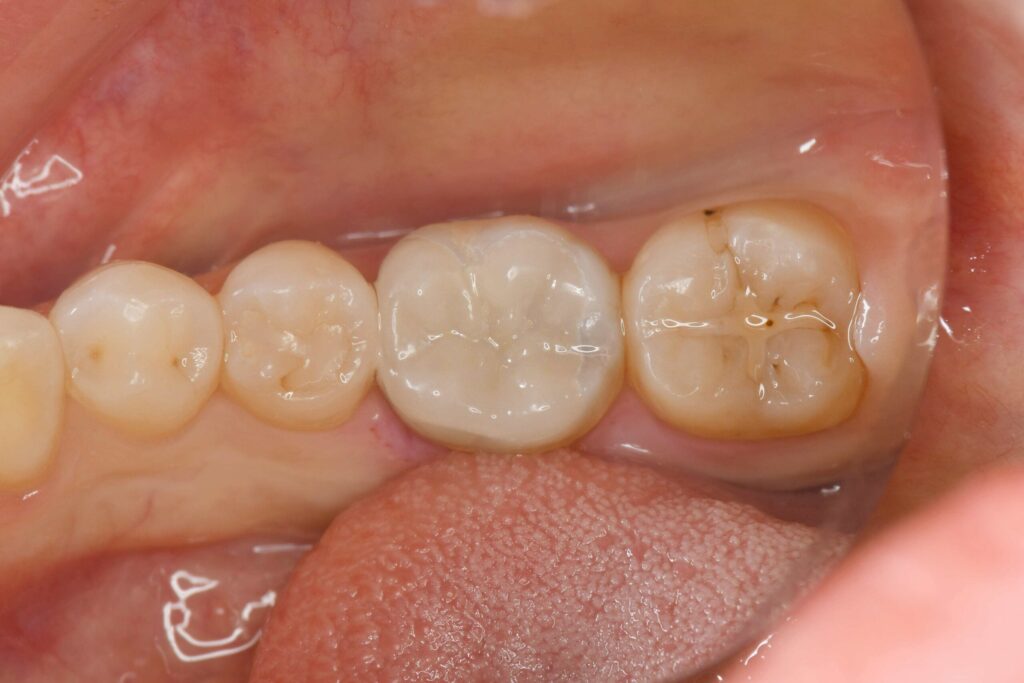

治療後のお写真です。

隙間なく歯と接着できていることがわかります。